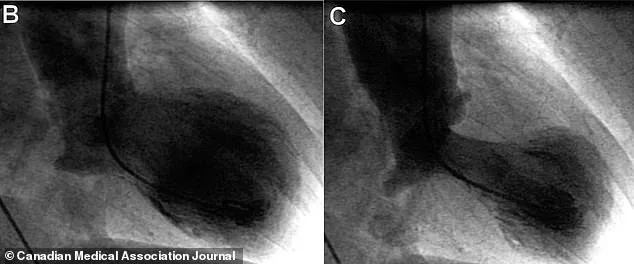

The condition is most frequently triggered by intense physical or emotional distress, such as the loss of a loved one, a sudden illness, or even the joy of a major life event. It can strike without warning, often leaving victims with crushing chest pain, shortness of breath, a racing heartbeat, and even fainting. These symptoms are so severe that they often lead to emergency room visits and invasive diagnostic procedures, such as cardiac catheterization, to rule out a real heart attack. Yet, unlike a heart attack, broken heart syndrome does not involve blocked arteries or permanent damage to the heart muscle. Instead, it is a temporary weakening of the heart, often caused by a sudden surge of stress hormones like adrenaline.

Despite its alarming symptoms, broken heart syndrome is not a fatal condition. Studies suggest that fewer than 1% of patients die from it, compared to 12-15% of those who experience a heart attack. This stark contrast underscores the importance of accurate diagnosis. Doctors often begin by assuming the worst, conducting tests like echocardiograms and blood work for troponin, a protein that leaks into the bloodstream when the heart is damaged. However, the definitive diagnosis requires a cardiac catheterization to confirm that no blockages exist in the coronary arteries. Only then can a patient be told they are not having a heart attack, but instead, suffering from takotsubo cardiomyopathy.